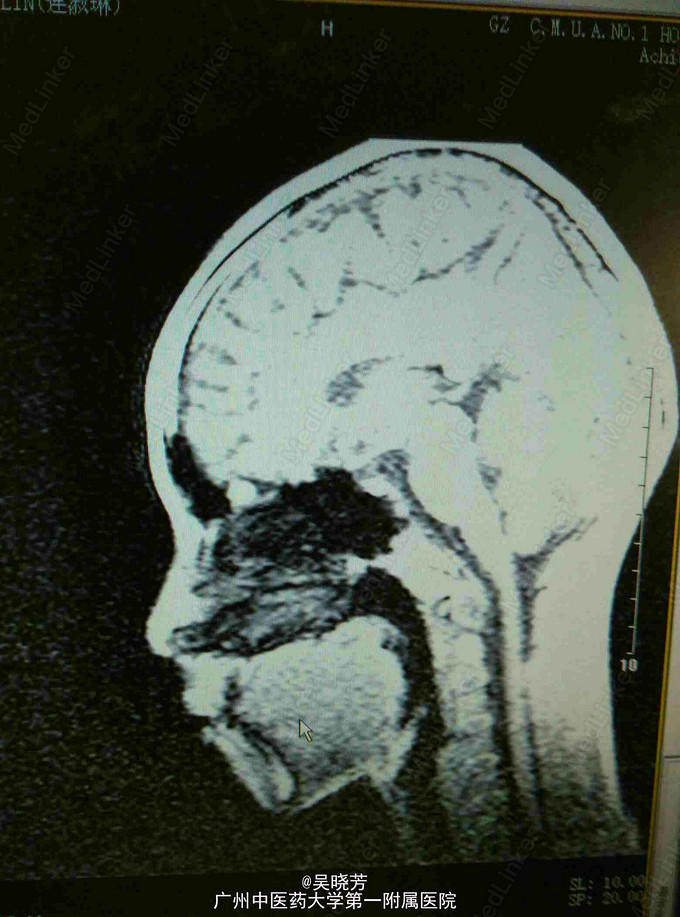

患者女,15岁。于1年前出现便秘,3天1次,伴食欲下降,时有腹胀腹痛,饭后明显,精神疲倦,体力差,食欲差,睡眠情况差,闭经,体重下降了15公斤。查体:腹部柔软,无压痛及反跳痛,,肝脾不大,肠鸣音减弱,2次/分

生命体征平稳,查体:腹部柔软,无压痛及反跳痛,,肝脾不大,肠鸣音减弱,2次/分。大便OB:阳性。性激素6项:基本正常,胃镜提示:胃下垂及十二指肠球部溃疡。垂体检查:未见异常。

便秘查因:十二指肠球部溃疡,胃下垂,继发性闭经。治疗:静滴奥美拉唑控制胃酸,口服阿嗪米特助消化,肠道益生菌调节菌群,中药汤剂健脾补气,清热散结。